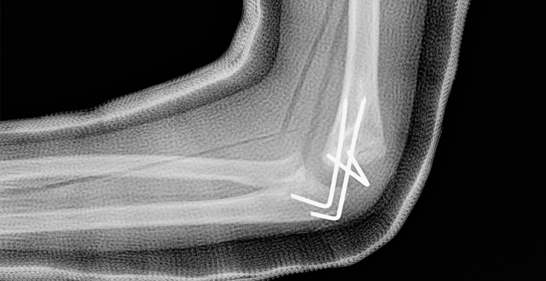

2. Elbow Fracture

A break in any of the three bones forming the elbow joint.

Icon Cause: Falls on an outstretched hand, direct trauma.

Icon Symptoms: Pain, swelling, and limited arm movement.

Icon Treatment: Splinting, casting, or surgery for displaced fractures.